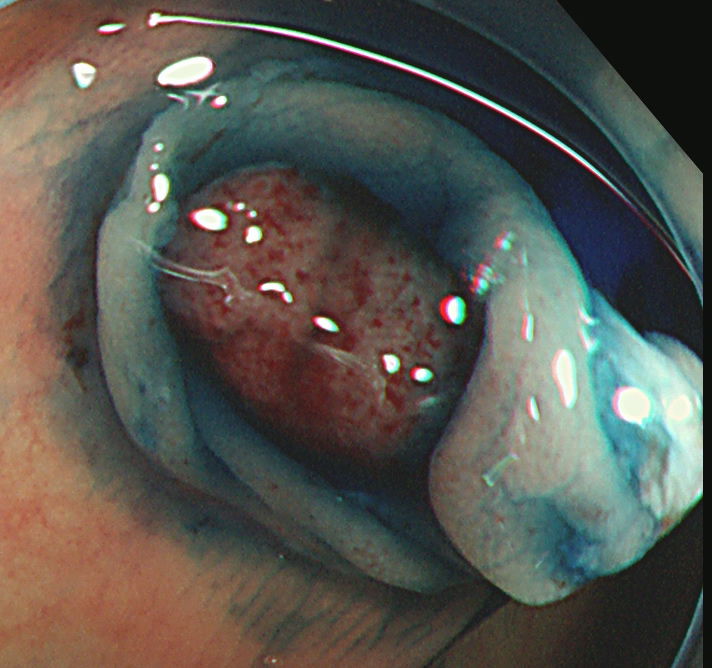

実際の写真です。

「生切り」なので、当然、内視鏡中(切除時)は出血します(患者さんが不安になります)。しかし、出血は数分で止まり、晩期出血は、まずありません。

取り残しを防ぐために、周囲に十分な余裕を持って大きく切除する必要があります(「ジャスト・サイズ」の傷では境界線上に腫瘍細胞が残ります)。そのために独特の「コツ」が必要で従来の方法よりも技術的に難しく時間がかかります。

コールド法で切除された検体は「目玉焼き」のようになります。「黄身」が病変で、「白み」が周囲の正常組織(余白、マージン)です。

腫瘍の取り残しを防ぐために「白み(余白)の大きな目玉焼き」にすることが、コールド法の最大のポイントであり、技術的に最も難しい部分です。